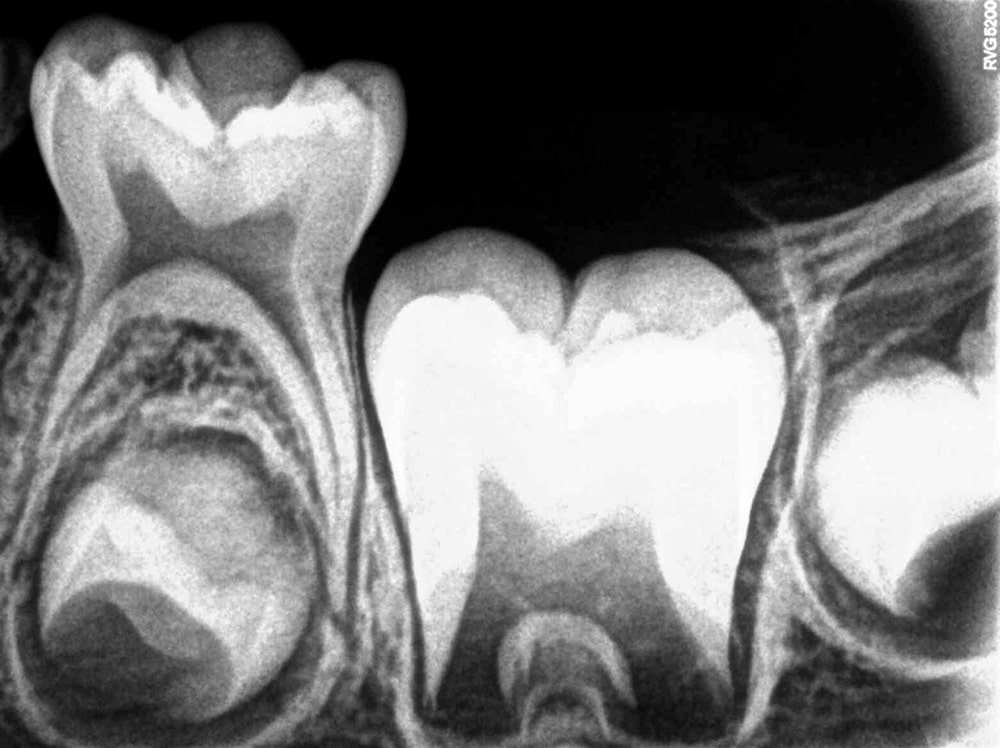

- Intraoral: Bitewing, periapical, occlusal - detailed views inside your mouth

- Detecting and analyzing cavities, especially between teeth

What to Expect During the Intraoral Xray imaging

- A sensor is gently placed inside or near your mouth

- You’ll be asked to stay still for a moment

- The sensor captures the X-ray and sends it to our computer instantly

- Your dentist reviews and discusses the images with you